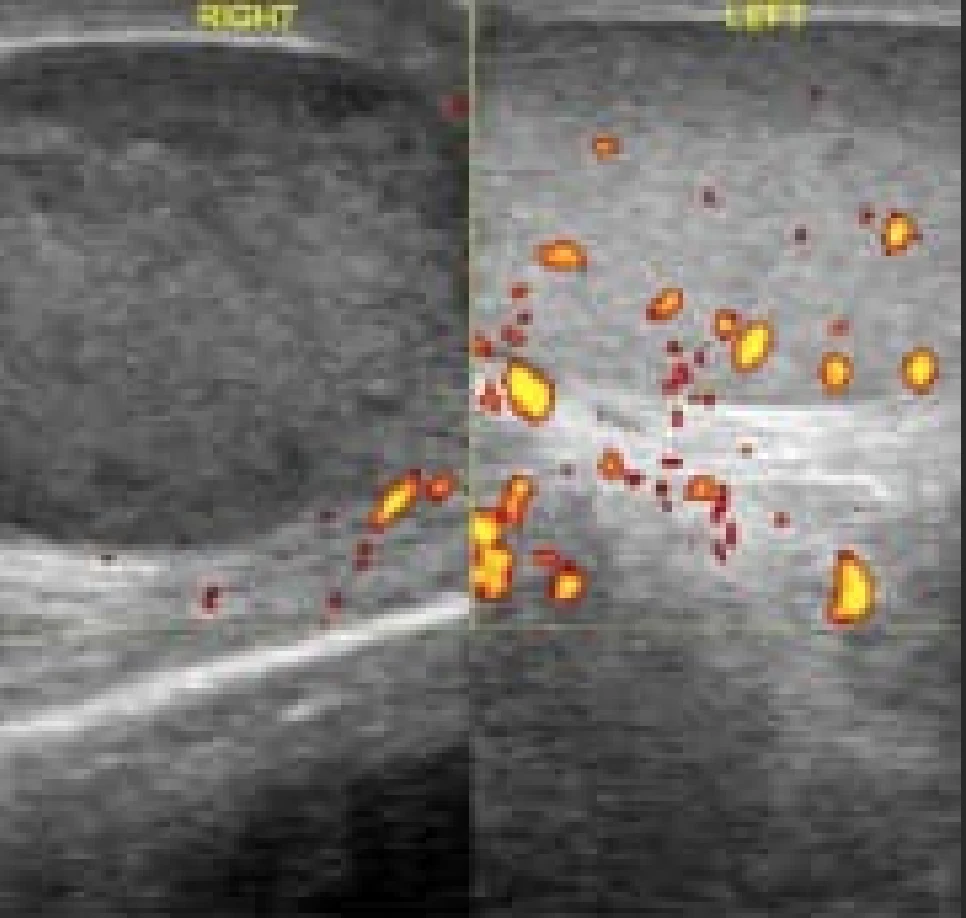

Un patient de 19 ans se présente aux urgences, un samedi soir 4 heures après l’apparition d’une douleur brutale au niveau du testicule. Vous effectuez cette échographie scrotale en attendant l’arrivée de l’urologue :

Quelle technique est la plus utile pour traiter (provisoirement) la pathologie et diminuer les douleurs ?